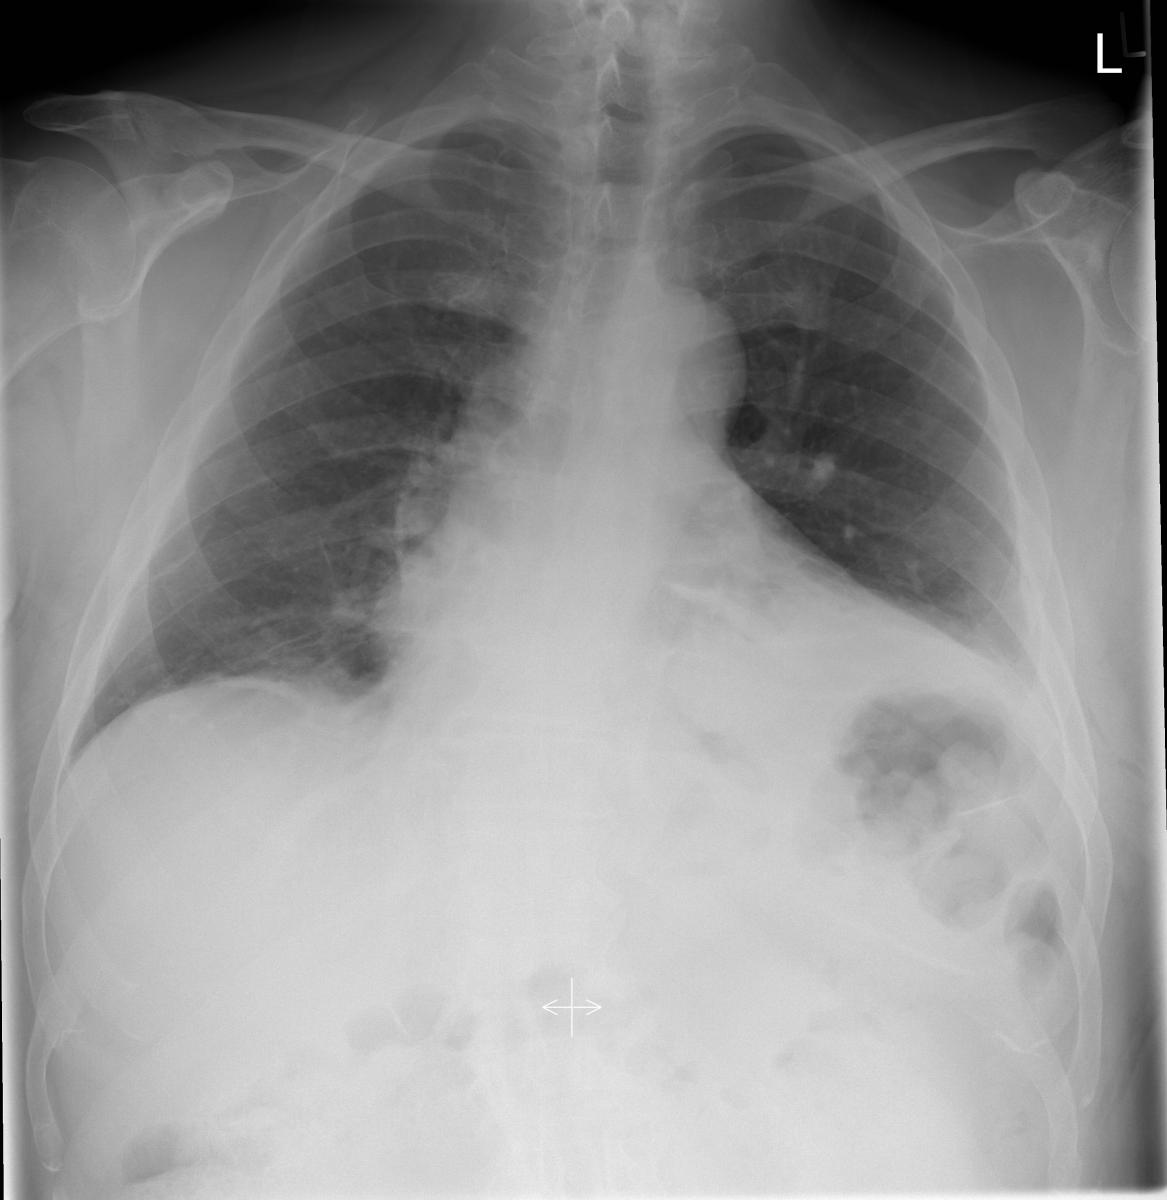

Figure 2: Post-operative day two CXR of the patient after the diaphragm plication. |